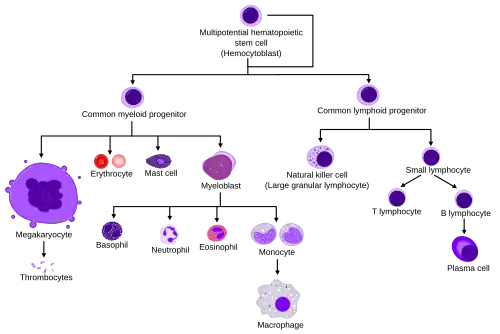

They are formed from stem cells in the bone marrow and differentiated into subpopulations of neutrophil-killers and neutrophil-cagers. They are short-lived (between 5 and 135 hours, see § Life span) and highly mobile, as they can enter parts of tissue where other cells/molecules cannot. Neutrophils may be subdivided into segmented neutrophils and banded neutrophils (or bands). They form part of the polymorphonuclear cells family (PMNs) together with basophils and eosinophils.[4][5][6]

Additional images

Blood cell lineage

Blood cell lineage -

_diagram_en.svg.png) More complete lineages

More complete lineages